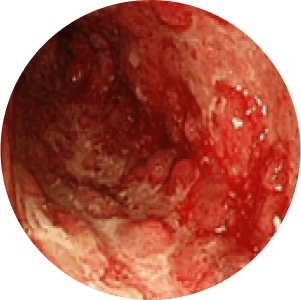

Stages of Ulcerative Colitis

stage

Noraml Mucosa

Mild Inflamation

Modearte Inflamation

Severe Inflamation